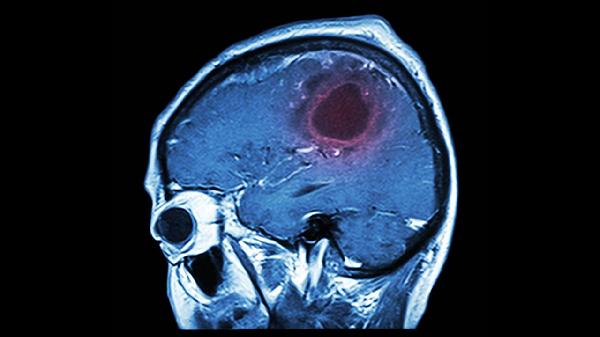

大脑前额叶功能受损可能导致注意力困难、决策障碍以及情感不稳定。锻炼大脑前额叶的有效方法包括认知训练、运动锻炼和健康饮食。